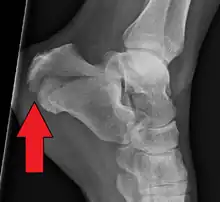

Diagnóstico

A suspeita surge no exame físico e é confirmada com radiografias convencionais ou com tomografia. Radiografia convencional é geralmente a ferramenta de avaliação inicial quando se suspeita de uma fratura do calcâneo. As radiografias recomendadas são (a) axial, (b) anteroposterior, (c) oblíqua e (d) com flexão dorsal e rotação interna do pé. Entretanto, a radiografia convencional é limitada para visualização da anatomia do calcâneo, especialmente na articulação subtalar, que é melhor visualizada com uma tomografia.[2]

O Ângulo de Gissane, ou "Ângulo Crítico", é o ângulo formado pelas encostas descendente e ascendente da superfície superior do calcâneo. Em uma radiografia lateral, um ângulo de Gissane> 130 ° sugere fratura da superfície da articulação subtalar posterior. O ângulo de Bohler, ou o "Tuber Angle", é outro marco anatômico normal visto nas radiografias laterais. É formado pela intersecção de 1) uma linha desde o ponto mais alto da faceta articular posterior até o ponto mais alto da tuberosidade posterior, e 2) uma linha a partir do primeiro até o ponto mais alto da faceta articular anterior. O ângulo de Bohler é normalmente de 25 ° a 40 °. Um ângulo diminuído é indicativo de uma fratura do calcâneo.[3]